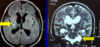

Size of tissue cysts in cysticercosis? where are they found?

1-2cm

Muscle (palpable) - eventually form calcified streaks

brain - seizures

Neurocysticercosis